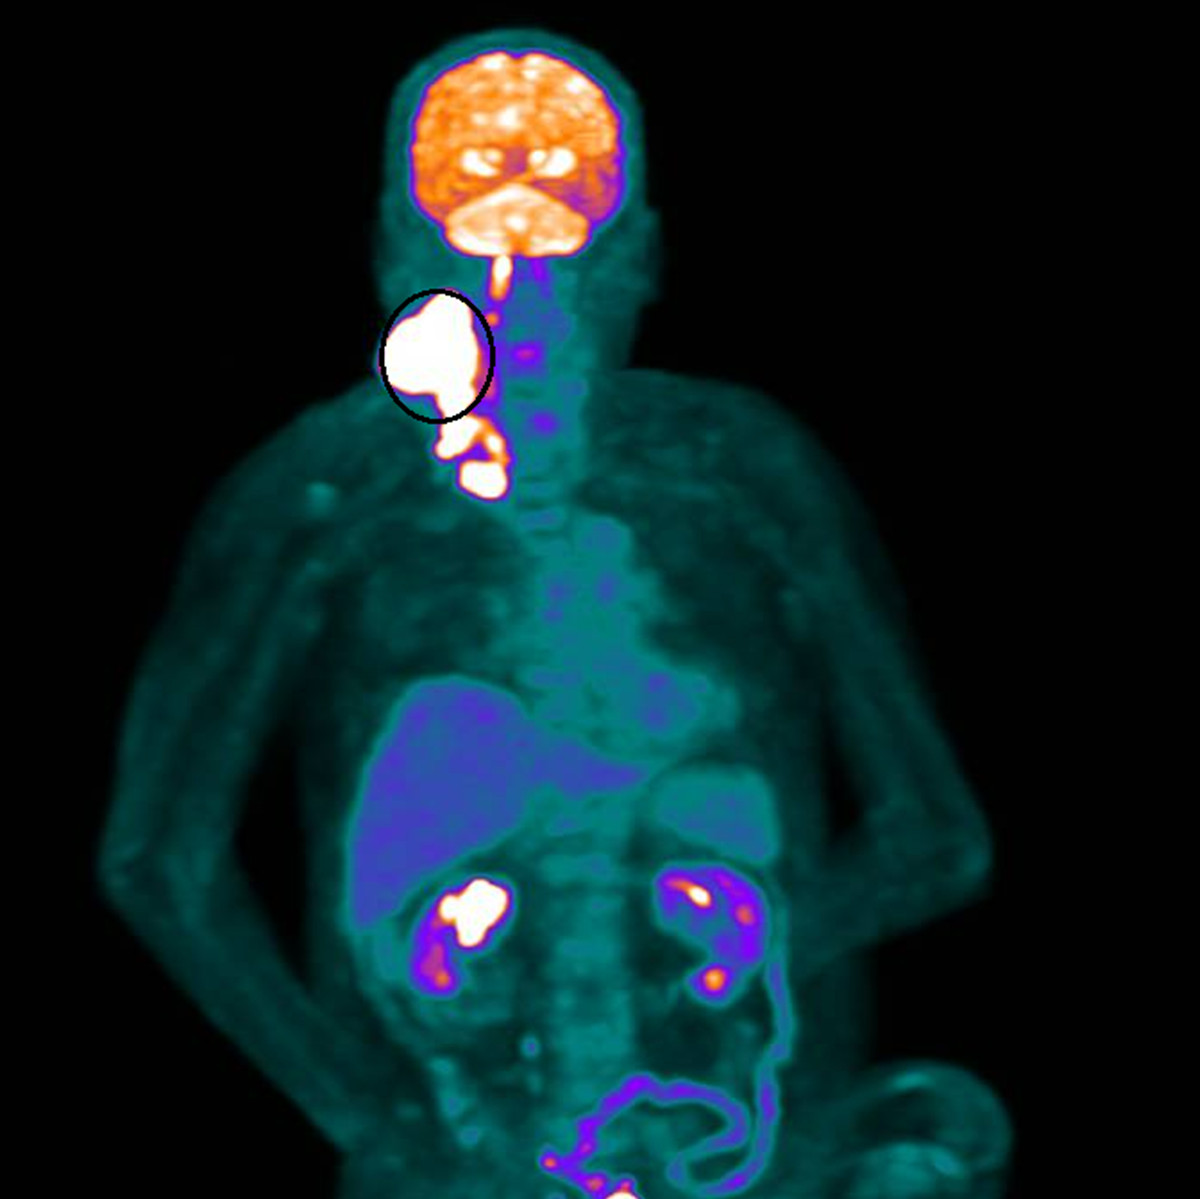

彰化醫院放射腫瘤科醫師張博竣說,80歲的林先生年輕時菸酒不離身,長年飽受高血壓所苦,10年前更因出血性腦中風復原不佳,自此臥床,長期居住在安養中心。原以為人生已趨於平靜,命運卻再次嚴峻考驗,4個月前其右側頸部被發現一顆約10公分大的腫瘤,檢查結果是第4期頭頸癌。

林先生隨即展開為期兩個月、共35次俗稱「電療」的放射線治療。療程結束後,原本巨大、外觀明顯的腫瘤幾乎完全消失,治療反應遠超預期。這個結果,不僅讓醫療團隊振奮,也為家屬帶來久違的笑容。